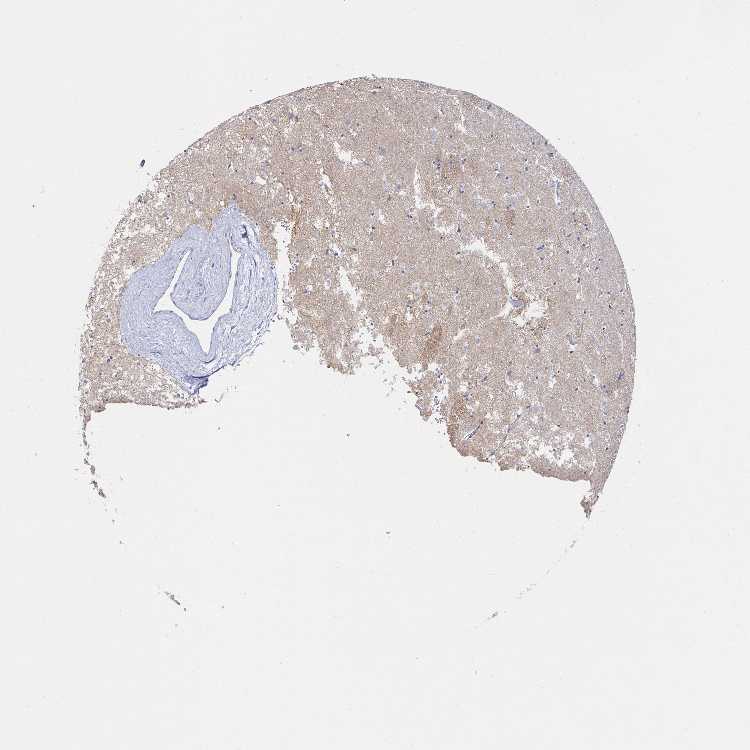

CAUDATE - Antibody stainingi

Antibody staining in the annotated cell types in the current human tissue is reported as not detected, low, medium, or high, based on conventional immunohistochemistry profiling in selected tissues. This score is based on the combination of the staining intensity and fraction of stained cells.

Each image is clickable and will lead to virtual microscopy that enables deeper exploration of all samples and also displays staining intensity scores, fraction scores and subcellular localization as well as patient and tissue information for each sample.

Antibody HPA042638Antibody HPA045752Antibody HPA049368Antibody CAB016793

Glial cells Not detectedNot detectedNot detectedNot detected

Neuronal cells Not detectedNot detectedNot detectedNot detected